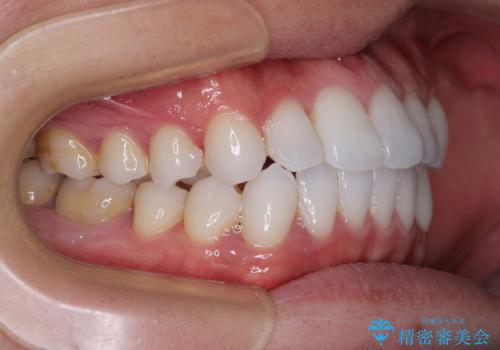

前歯のクロスバイトを改善 インビザラインによる矯正治療

- 前歯のクロスバイトを気にして来院された患者様です。

デコボコやクロスバイトが散見されたため、IPR(歯と歯の間を削る)によってスペースを獲得できるように設計し、インビザラインにより治療を行うこととしました。

今回は、ワイヤー装置を併用することなく治療を行い、トラブルなく、満足のいく歯列に整えることができました。

矯正治療の途中でホームホワイトニングを併用され、術前とは見違えるほどきれいな口元となりました。